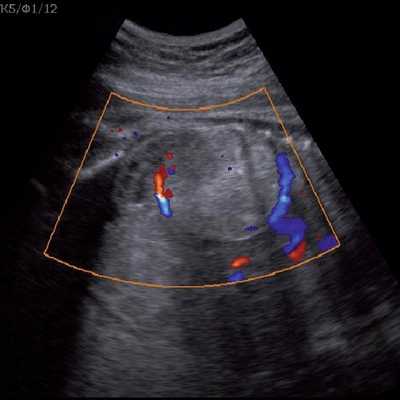

Под диафрагмой справа визуализировалось гиперэхогенное опухолевидное образование несколько неоднородной солидной структуры, с четкими ровными контурами, размером 50x38x35 мм. К нижнему полюсу данного образования прилежала правая почка, имеющая нормальные размеры, форму и структуру. Нижняя полая вена была смещена кпереди и влево. Обращала на себя внимание выраженная гепатомегалия, причем структура печени не была однородной. Она содержала множественные гиперэхогенные включения размерами до 17 мм, окруженные тонким гипоэхогенным периферическим ободком. Цветовое допплеровское картирование(ЦДК) демонстрировало интенсивную периферическую васкуляризацию опухоли (рис. 1-3).

Рис. 2. Кровоток в нейробластоме плода. Цветовое допплеровское картирование. Отчетливо виден питающий сосуд, огибающий образование по его периферии. К нижнему полюсу образования прилежит интактная почка плода.

Кровоизлияние в надпочечники, как правило, выглядит эхогенным или неоднородной структуры образованием, иногда может быть полностью анэхогенным и характеризуется изменением ультразвуковой картины при динамическом исследовании, постепенно превращаясь в анэхогенное кистозное образование, в котором с течением времени отмечается утолщение его стенки [13] и образуются кальцификаты. Энергетический допплер демонстрирует полную аваскулярность такого образования. В нашем случае образование имело повышенную эхогенность, несколько неоднородную структуру. При ЦДК в опухоли регистрировался преимущественно периферический кровоток.